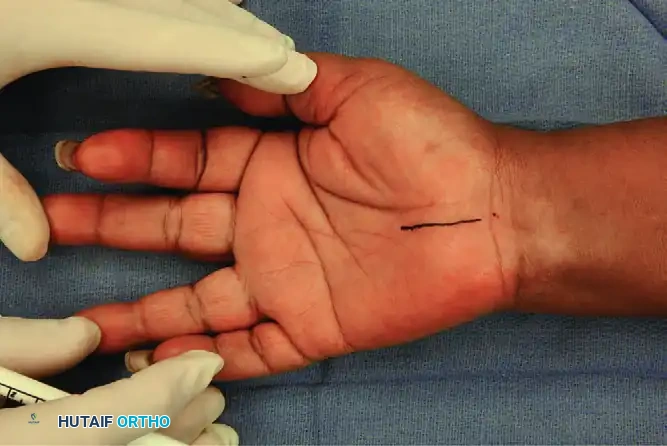

Step 1: Incision Planning and Marking

Proper incision placement is the most critical step in avoiding the PCBMN and the recurrent motor branch.

* Mark the planned surgical incision with a sterile skin pen.

* The longitudinal incision should begin just distal to the distal wrist flexion crease.

* Position the incision slightly ulnar to the midline of the wrist (using a center dot reference point).

* Extend the incision distally for exactly 3.0 cm, keeping it strictly in line with the third web space (the axis of the ring finger).

Surgical Note: Only rarely is it necessary to extend the incision proximally into the distal forearm. If proximal extension is required, angle the incision ulnarly to avoid crossing the wrist flexion creases at a right angle and to stay clear of the PCBMN.

The incision is marked with a skin pen, extending 3.0 cm distally in line with the third web space.